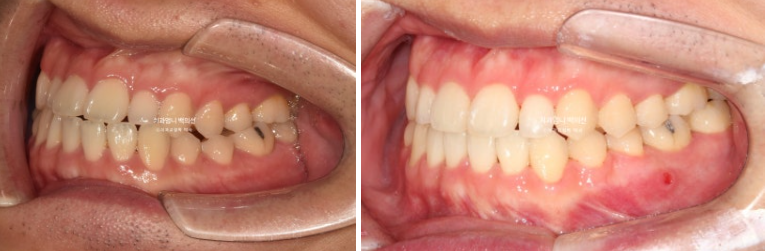

치료 시작 10개월차 모습입니다. 교정용 나사인 미니스크류를 아래쪽에 심고 사랑니 공간으로 밀어냅니다.

24.11

치료시작 1년 5개월 차 치료를 마무리 했습니다.

25.06

중심선은 잘 맞고 한쪽 어금니 반대교합은 별도의 악궁확장 없이 좋아졌습니다.

24.01~25.06

결손된 작은어금니 쪽으로 쓰러져 있던 큰어금니는 잘 세워졌습니다.

교합은 좋습니다.